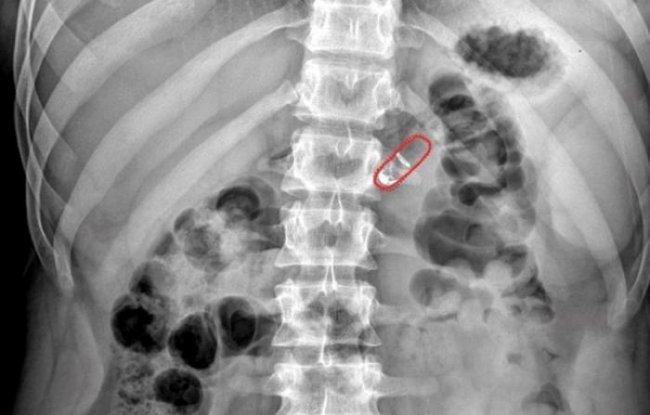

Испытания «умной капсулы» RaniPill с различными потенциально полезными препаратами, включая инсулин, проводились на сотне подопытных животных. Все оказались успешными. Кроме того, успешно закончились и тесты с участием 20 людей-добровольцев, поделенных на две группы. Однако в этом случае команда Имрана обошлась без препаратов, лишь проверив ощущения добровольцев от применения «умной капсулы». Одну группу попросили принять капсулу сразу после еды, вторую – на голодный желудок. После того, как люди глотали капсулы им разрешили свободно ходить и вообще заниматься привычными делами. Каждые 30 минут участникам эксперимента делали рентген желудочно-кишечного тракта, на котором был изображен прогресс перемещения капсулы.